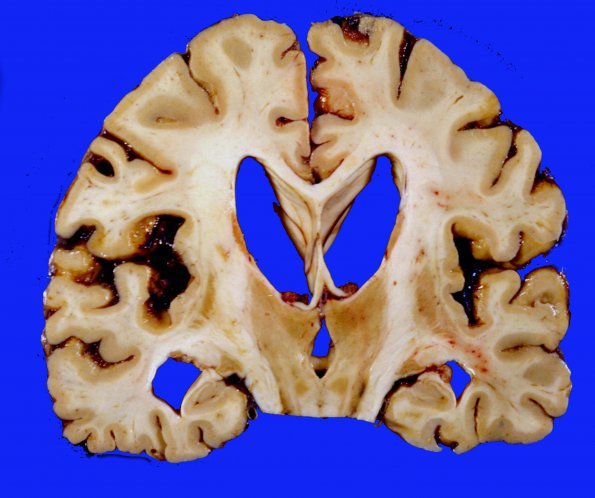

15A3 CJD (Case 15)  3 extended survival

Additional example of gross neuropathology.